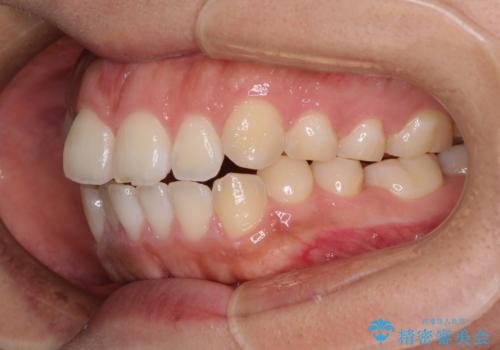

- 口が閉じにくさを気にして来院された患者様です。

上下の前歯が前方に突出していたため、上下左右の第一小臼歯4本を抜歯し、ワイヤー装置にて抜歯矯正を行うこととしました。

上下前歯部の被蓋関係を改善するの時間がかかり、3年間を要することとなりましたが、スッキリとした口元に仕上がりました。